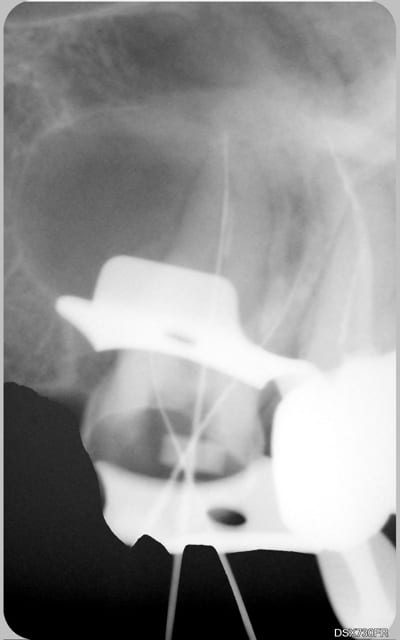

15/10/2008 à 16h17

tu veux des images...en voilà 2...avant traitement et 6 mois plus tard...

12 03 2008 g2x3kb - Eugenol

25 08 2008 fya484 - Eugenol

C'est un beau début de cicatrisation.

Un début de guérison c'est léger pour un fil lu 1463 fois.

Mais je veux bien croire qu'il y en a d'autres, j'aimerais juste en voir.

Toi, pour commencer, t'as bien une image de guérison complête !!!!!